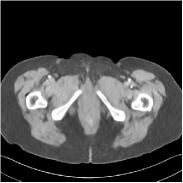

Fig. 2 shows a test example reconstructed using various methods.

Refer to caption

Figure 2: Reconstructions of slice 100 from patient L192 using various methods. The display window is [800 1200] HU.

We observe that PWLS-EP reduces the severe noise and streak artifacts observed in the low-dose FBP images, and the transform learning-based method PWLS-ULTRA further suppresses noise and reconstructs more details of the image such as the zoom-in areas. However, both methods have some blurry artifacts. The standalone FBPConvNet method heavily removes noise and streak artifacts, while introducing several artificial features (e.g., feature indicated by the arrow in the top-right box in Fig. 2). WavResNet denoises the image without introducing artifical features, but still retains some streaks around image boundaries and blurs some details (e.g., feature indicated by the arrow in the bottom-left box in Fig. 2). The state-of-the-art MAP-NN method performs slightly better than WavResNet in terms of suppressing streak artifacts, while it still loses some details as indicated in the zoomed regions. The competing plug-and-play unrolled method—ADMM-Net with WavResNet denoiser—outperforms the standalone WavResNet method, but still has some streak artifacts and blurred details. Compared to these methods, the proposed SUPER methods (SUPER-WRN-EP, SUPER-WRN-ULTRA, SUPER-FCN-EP, and SUPER-FCN-ULTRA) improve the reconstruction quality in terms of removing noise and artifacts, and recovering details more precisely. Two other example comparisons are included in the supplement (Fig. 10 and Fig. 11).